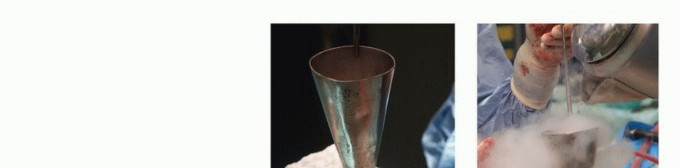

تقنية الصب المباشر بالنيتروجين السائل: تفاصيل الإجراء

تعتبر تقنية الصب المباشر بالنيتروجين السائل (Direct Pouring Liquid Nitrogen Technique) في العلاج بالتبريد لأورام العظام من التقنيات المتقدمة التي تتطلب دقة عالية وخبرة جراحية متخصصة. يفضل الأستاذ الدكتور محمد هطيف هذه التقنية نظرًا لفعاليتها في تحقيق تجميد عميق وشامل للورم، مع الحفاظ على الأنسجة السليمة المحيطة.